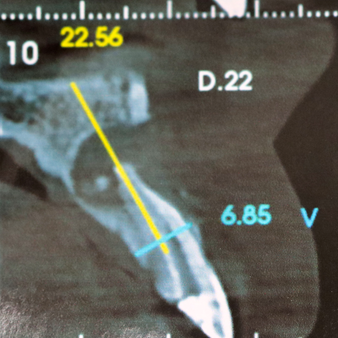

Após o exame tomográfico, observou-se uma lesão importante com ausência óssea apical e vestibular.